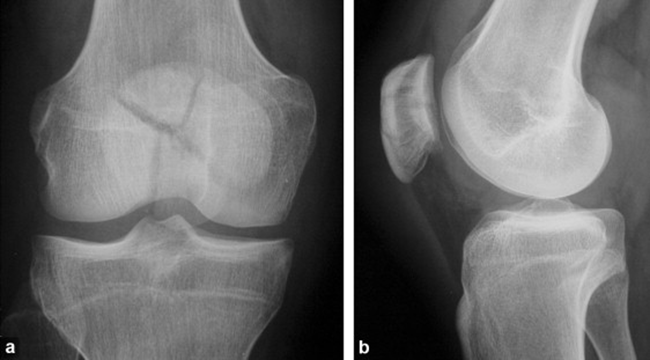

Stellate Fracture

•Fracture lines radiate form a central point of injury with a star like pattern

•Cause: Trauma - falling onto knees, knees hitting dashboard

•Complications: pain, weakness, infection, stiffness

•Radiographic appearance: comminuted fracture with a star like pattern

•No manual exposure factor change

• Prognosis/Treatment – Non operative and Operative